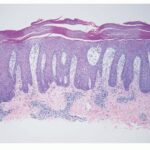

Atlas of skin histopathology

Epidermal hyperplasia = فرط تصنع البشرة